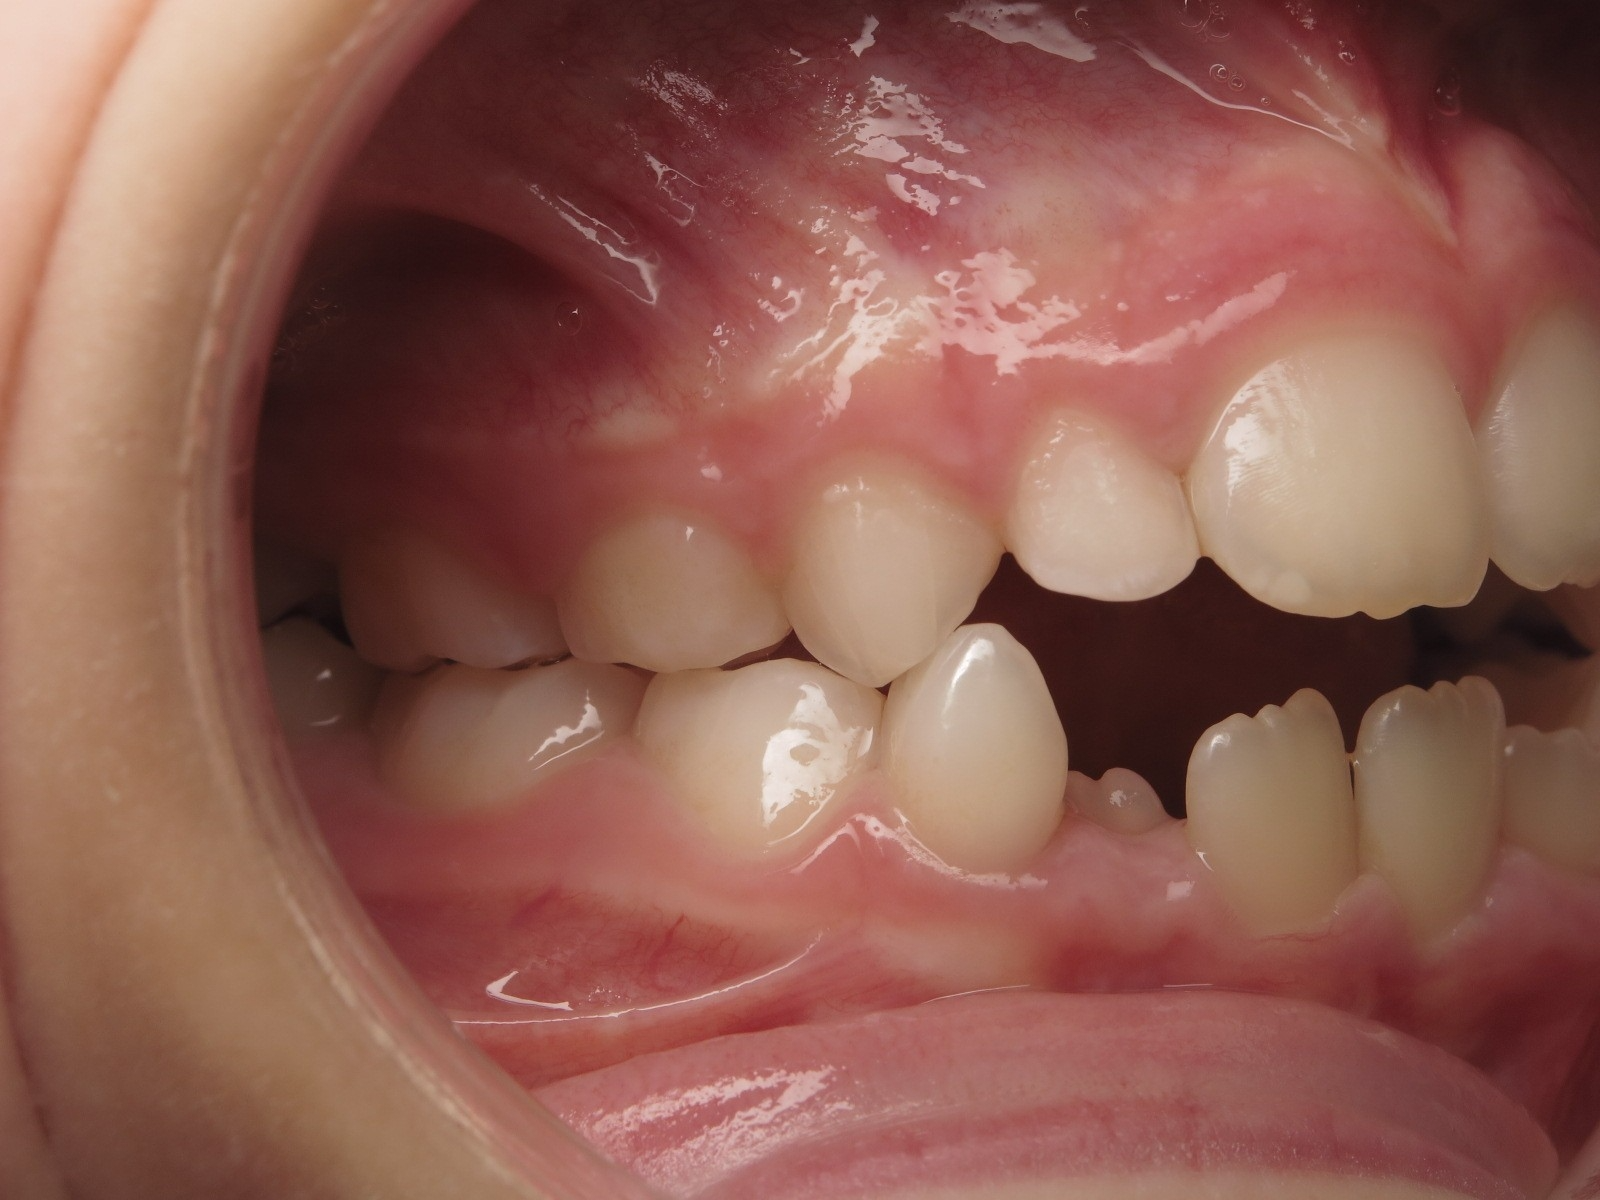

surveillance évolution de la dentition pendant 27 mois

appareillage mobile pendant 14 mois